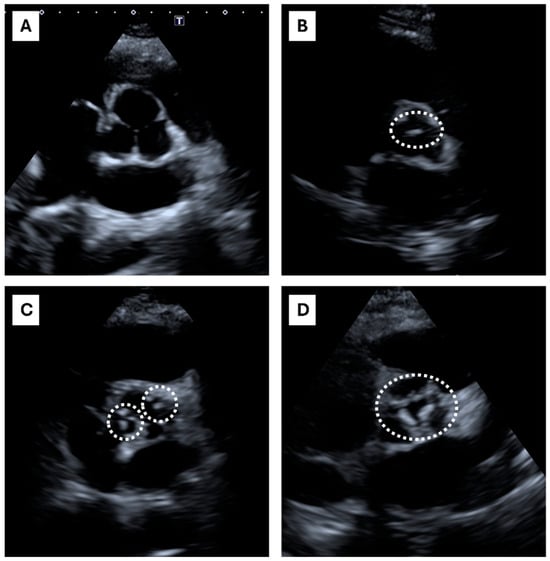

2.2. Echocardiographic Calcium Score (ECS)